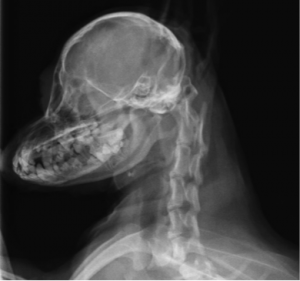

術前レントゲン

レントゲンより軸椎の背側棘突起と環椎間にて間隙があり、VD像にて歯突起の低形成が確認されました。MRIでも環軸椎間にて脊髄の高信号があり典型的な環軸椎亜脱臼症と判断されます。また、この症例では環椎の頭蓋内への陥入があり環椎後頭骨オーバーラッピングが存在すると思われました。人医療とは異なり動物に対する治療はまだわかっていないために環軸関節の固定のみを実施しました。